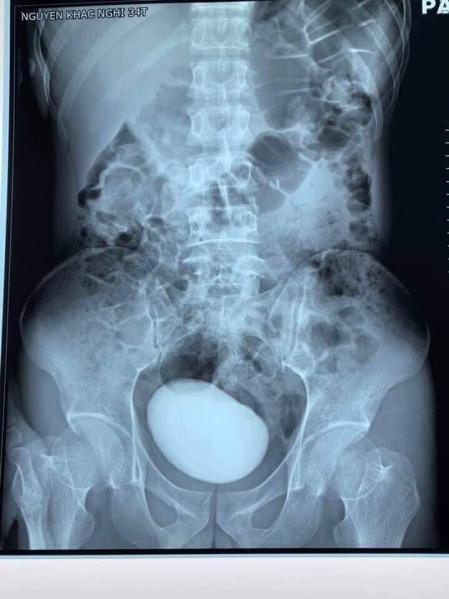

Las redes sociales en Vietnam están que arden por las peculiares imágenes de un enorme cálculo de vejiga que le ha sido extraído a una mujer de 34 años en los últimos días. De acuerdo con diferentes medios vietnamitas, todo comenzó cuando la mujer acudió al servicio de urgencias del H ospital General Phu Binh, en Thay Nguyen, quejándose de un intenso dolor abdominal. Tras un breve examen en el que los especialistas pudieron notar cómo su abdomen estaba más duro y tenso de lo normal, decidieron hacerle una tomografía (CT) para obtener una imagen más precisa de lo que había en su interior. Lo que no se esperaban, sin embargo, era encontrarse con una enorme masa redonda alojada en su abdomen.

Ante este resultado, los especialistas le confirmaron a la mujer que iban a practicarle una cirugía de emergencia para examinar y extraer lo que quiera que fuese que tenía en su interior. Durante la operación, los cirujanos extrajeron un cálculo de más de diez centímetros de largo, cuyo peso superaba los 400 gramos.